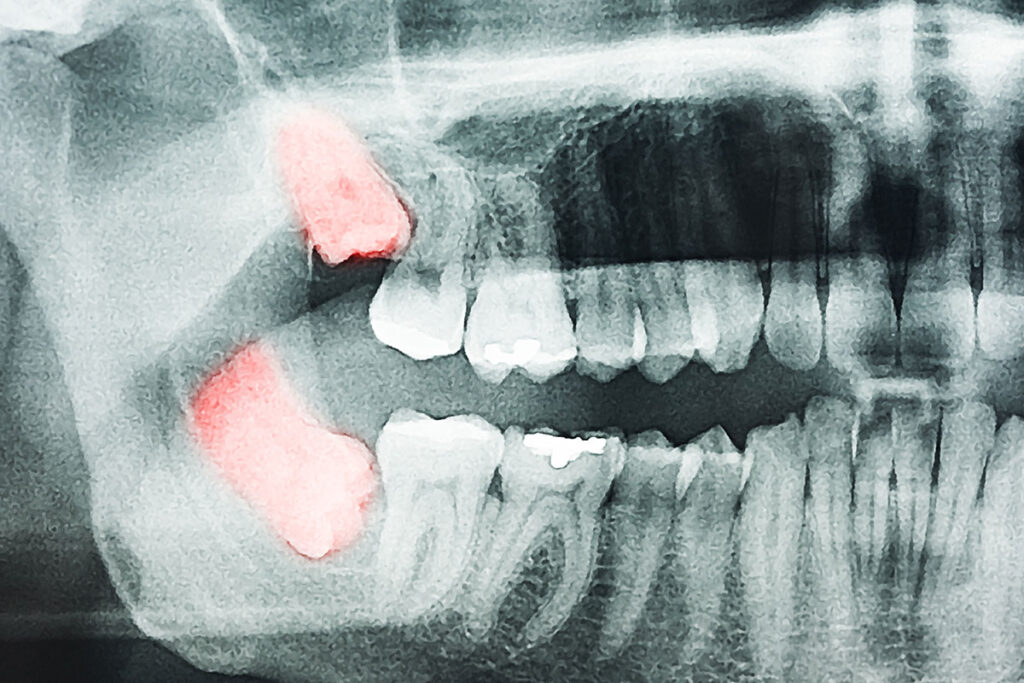

20’lik Diş Nedir?

20’lik diş, genellikle 17-25 yaş aralığında çıkan ve ağızda en son görülen azı dişleridir. Tıbbi adıyla “üçüncü büyük azı dişleri” olarak da bilinir. Çene yapısının küçülmesiyle birlikte bu dişlerin çıkması çoğu kişide sorunlara yol açabilir. Kimi zaman sorunsuz şekilde ağızda yerini alırken, kimi zaman gömülü kalır veya eğri çıkar. Bu durum da diş sağlığını olumsuz etkiler.